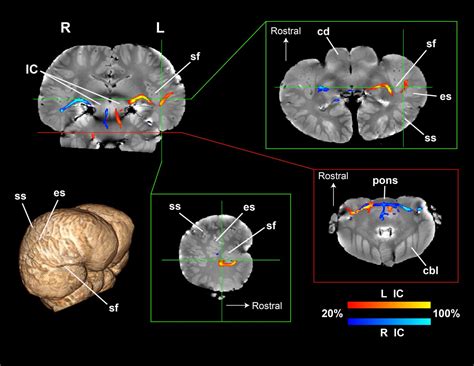

Advanced imaging techniques, such as magnetic resonance imaging (MRI) and functional MRI (fMRI), provide detailed insights into the structure and function of the dolphin brain. These techniques allow researchers to study the neural basis of dolphin cognition and behavior, identifying specific brain regions and neural pathways involved in different cognitive abilities. Genetic studies can also provide valuable information on the genetic basis of dolphin cognition and behavior, helping to understand the evolutionary origins of their advanced cognitive abilities.